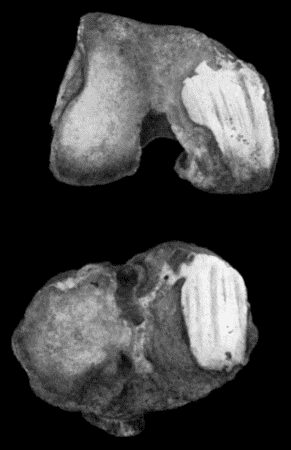

166.Radiogram of Multiple Loose Bodies in Knee-joint 540

167.Loose Body from Knee-joint 541